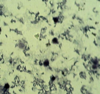

**Cryptosporidium**-oocysts in smear

58

**Cryptosporidium**-oocysts in smear

59

**Cryptosporidium**-oocysts in smear

60

**Cryptosporidium**-oocysts in smear